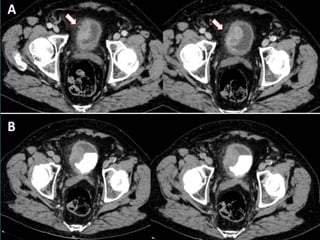

• #43 CARCINOMA DE CÉLULAS TRANSICIONALES PIÉLICO. Imágenes axial y coronal en FN que muestran formación sólida hipercaptante ocupando pelvis renal izquierda. En las imágenes axial y coronal en FE la lesión se identifica como un defecto de repleción.

• #44 CARCINOMA URETERAL DISTAL DERECHO. Imágenes coronales de TCMD que muestran tumoración sólida endoluminal ocupando uréter distal derecho (flechas).